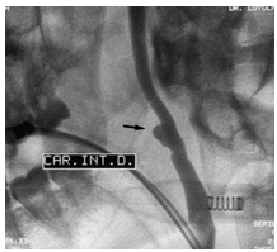

Se realizó una TC facial y cervical con contraste intravenoso (i.v.) apreciándose una fractura de la porción horizontal de la rama mandibular derecha con gran desplazamiento lateral y gran hematoma que ocupaba la parte lateral derecha del cuello. Llamaba la atención la pérdida de nitidez de los vasos en las ramas carotídeas derechas, estando nítida la vena yugular homolateral (fig. 1). Con estos hallazgos se sospechó una afección carotídea realizándose una arteriografía que permitió visualizar un aneurisma postraumático a 4 cm del origen de la carótida interna derecha (fig. 2) y la sección de una rama distal de la arteria mandibular con fuga de contraste. Se procedió a embolización de ambas ramas, con buen resultado.

Figura 2. Arteriografía: carótida interna derecha que presenta un seudoaneurisma.